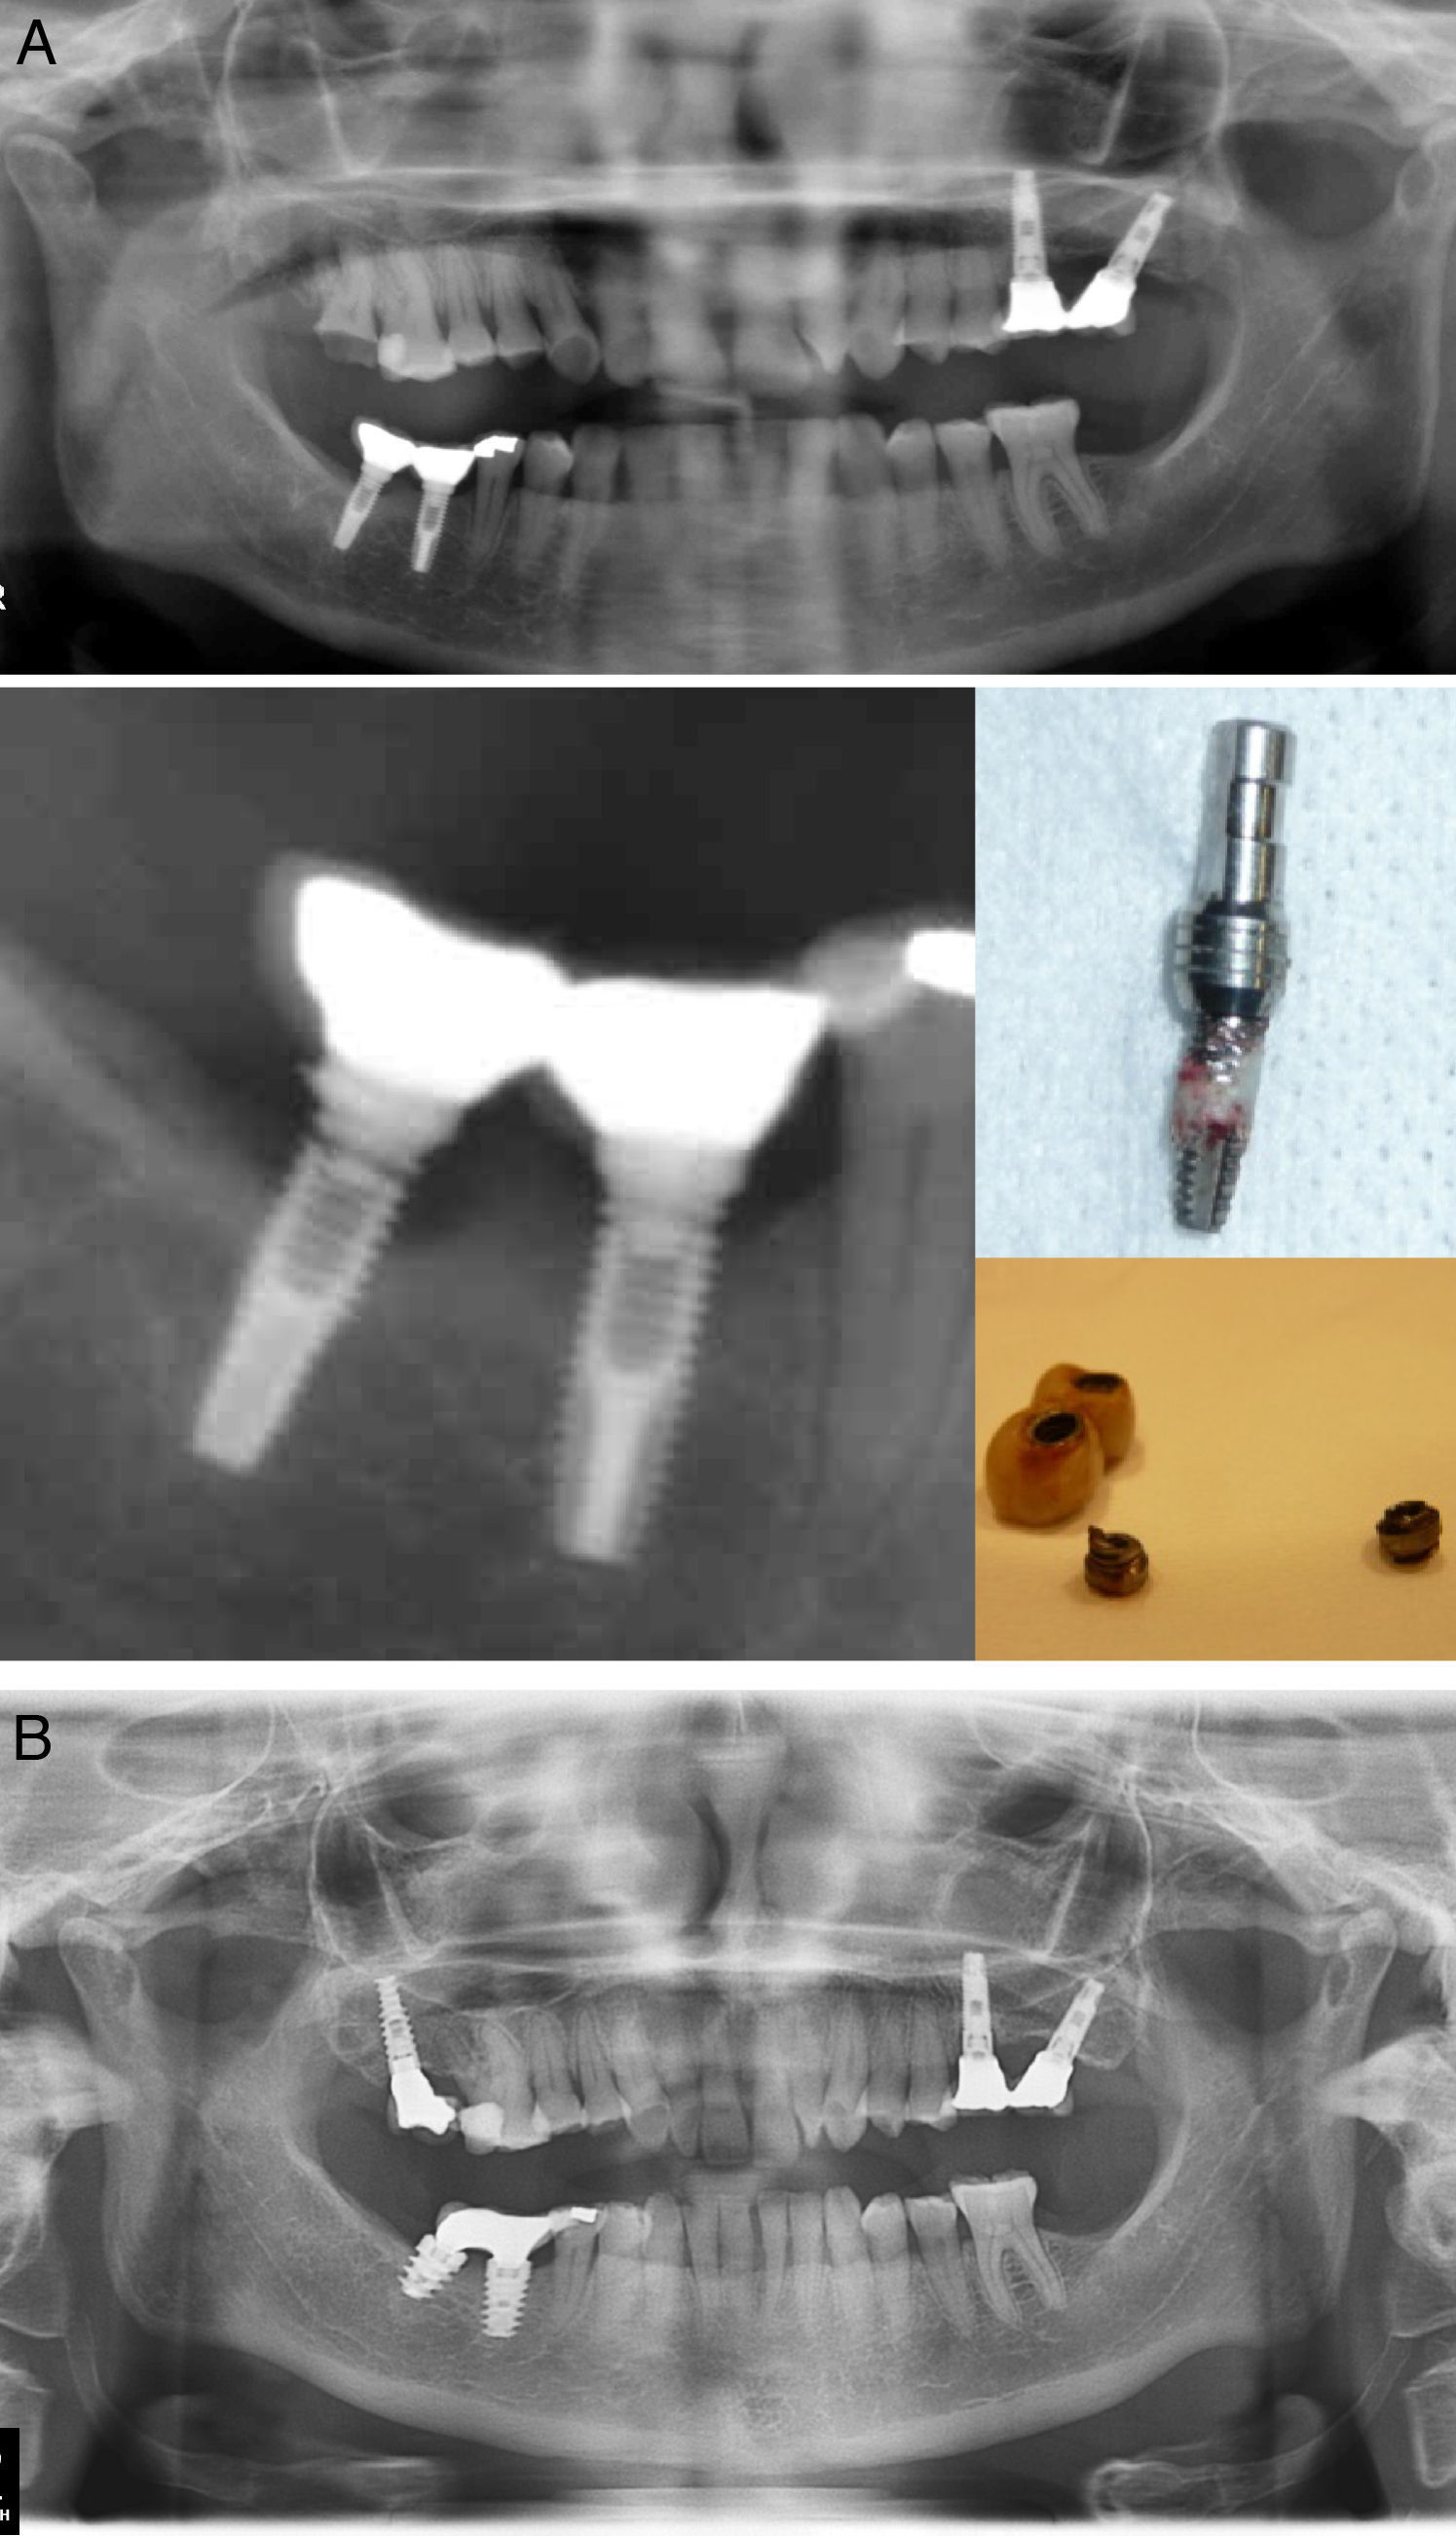

Figura 2.A) Mujer bruxista importante a los 3 años de carga funcional tras varios episodios de aflojamiento, presenta fractura de los implantes mandibulares. En la ortopantomografía se observa la reabsorción ósea de la región crestal, que normalmente precede a la FI la línea de fractura es perpendicular al cuerpo implantario, justo donde termina el tornillo protésico. Se realizó explantación de los remanentes mediante trefinas de hueso. B) Se colocaron 2 nuevos implantes de mayor diámetro, conexión interna, 3 años de seguimiento con 2 episodios de aflojamiento.

Podríamos decir que dado que los cantilever amplifican el estrés y, por lo tanto, son un factor de riesgo considerable para la FI, el sistema de conexión externa tal vez actúe como un cantilever vertical que magnifica el estrés aplicado sobre la prótesis favoreciendo la FI Además, esto explicaría la forma en que se fracturan los implantes de conexión externa, en los que la línea de fractura se encuentra en el plano axial (perpendicular al cuerpo del implante), justo por debajo del extremo del tornillo protésico (fig. 2); mientras que los de conexión interna suelen desarrollar una fractura «en estallido», grietas verticales de la plataforma del implante (fig. 3).